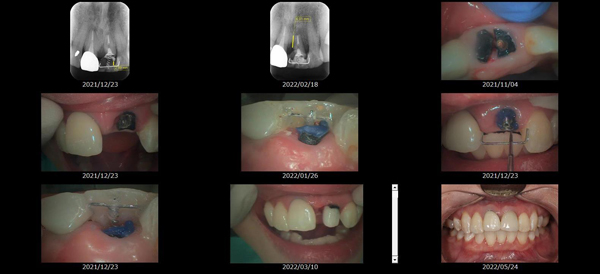

歯の形、歯並び、歯肉ラインが整う美しい口元

大掛かりな歯ぐきの手術や装置を使った矯正治療を行わずに、たった2回で歯並びをきれいに整えることができます。

BTAテクニック® とは

従来のセラミックで治すオールセラミックという被せ物や、セラミックを張り付けるラミネートべニアという方法に、歯科医師と歯科技工士の双方の手法と技法を癒合させることで、可能とした 歯ぐきのラインを2回の来院で、綺麗に仕上げ、歯の見た目も審美的に出来るテクニックのことである。

BTAテクニック® 以外の一般的な治療で歯ぐきのラインを整えるには、歯ぐきを切り、骨を削る手術をすれば可能ですが、歯ぐきの治りに数か月の期間が必要です。もしくは、矯正治療によって、歯並びを改善する方法、もしくは神経を抜いて、被せ物をするしかありません。

BTAテクニック® を用いると、歯ぐきや骨への手術が必要ない為に、治療期間が短縮でき、2回の来院で完了できるメリットがある。 また、この方法を用いることで、年々歯ぐきが下がって見た目が悪くなるということが起きにくくなる。歯周ポケットと言われる溝が浅くなり、歯ブラシが容易になる。などの利点が挙げられる特殊なテクニックである。

また、救歯BTAセラミックは、BTAテクニック®が持つ成功する理由(*)から、深い位置まで虫歯が進行してしまって歯を抜かないとならない歯に応用する事で、抜かずに治療することが出来る場合がある。

症例によっては、BTAテクニック® , 救歯セラミックが適応出来ない場合があります。 また、この方法を用いることで必ず歯が残せるという治療方法ではありません。

価格

> 1歯 165,000円